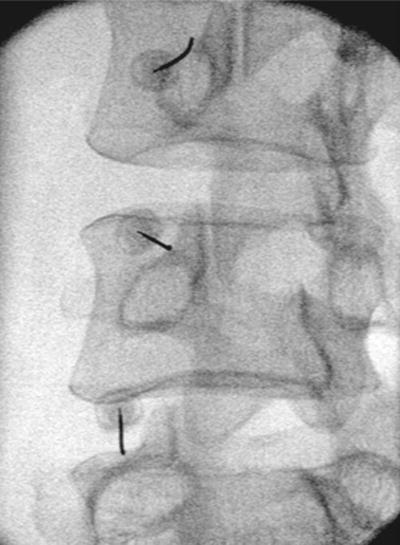

Πώς εκτελείται η διαδικασία νευρικού αποκλεισμού της άρθρωσης

Η διαδικασία μπορεί να διενεργηθεί στις αρθρώσεις του αυχένα, της ράχης και της μέσης. Με τον ασθενή σε πρηνή θέση και υπό τοπική αναισθησία εισάγεται μια βελόνα που υπό συνεχή ακτινοσκοπική καθοδήγηση φθάνει στους νευρικούς κλάδους της κάθε άρθρωσης. Μια μικρή ποσότητα αναισθητικού διαλύματος εγχέεται και αφαιρείται η βελόνα. Ο ασθενής αναπαύεται για 30 λεπτά και σε μία ώρα μπορεί να εξέλθει, μετά την αξιολόγησή του από τον θεράποντα ιατρό. Οι κίνδυνοι από τη διαδικασία είναι σπάνιοι.

Χορηγείται τοπική αναισθησία για να μουδιάσει το δέρμα. Ο ιατρός κάτω από ακτινοσκοπική καθοδήγηση, εισάγει μια λεπτή ειδική βελόνα που στοχεύει το σημείο διέλευσης του μέσου νευρικού κλάδου, το οποίο βρίσκεται στη συμβολή της άνω αρθρικής και της εγκάρσιας απόφυσης του σπονδύλου στην οσφυϊκή μοίρα.

Στην πορεία ακολουθεί κινητικός και αισθητικός ερεθισμός του νεύρου. Αυτό μπορεί να οδηγήσει σε μικρούς τοπικούς μυϊκούς σπασμούς και να προκαλέσει λίγο πόνο. Μόλις ελεγχθεί η σωστή τοποθέτηση της βελόνας, χορηγείται τοπικό αναισθητικό και ακολουθεί η θερμοκαυτηρίαση του νεύρου.